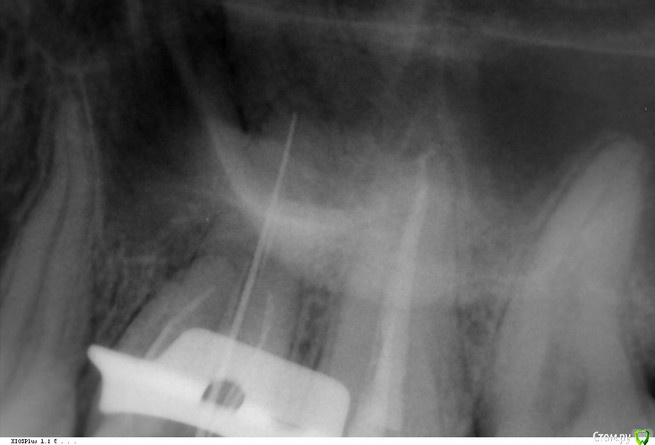

Викторри Опубликовано 16 февраля, 2018 Поделиться Опубликовано 16 февраля, 2018 Здравствуйте,уважаемые доктора и пациенты! Проблема 26 зуб, лечение по поводу пульпита в 2011г (если необходимо, могу прикрепить снимок).В ноябре 2017г обнаружена киста ,проявлявшаяся реакцией на горячее. В декабре 2017 за 3 сеасна открыты 3 и пройден 4 канал. В наст время готовлюсь к постоянной пломбировке (в каналах каласепт уже 8 недель). Меня смущает картина прохождения канала (вроде дистальный),к-ый самый длинный, а именно кажется,что не прошли его до верхушки.Вопросы :1. права ли я на счет не до конца пломбир. канала?Если да-что делать?2. необходимо ли нахождение Каалсепта такое длительное время в каналах? Очень жду ответа.Спасибо Ссылка на комментарий

Викторри Опубликовано 28 февраля, 2018 Автор Поделиться Опубликовано 28 февраля, 2018 Уважаемые доктора,здравствуйте! Прошу помощи в связи с новыми нюансами моего лечения:1) 19.02 за 2 часа до запланированного пломбирования каналов на постоянку мне позвонили из клиники и сказали,что врач сегодня не примет, у нее проблемы и когда примет выясняется. На след день сообщили,что док ушел из клиники и меня передают другому врачу.2)за 3 дня до этого 16.02 я взяла снимки,сделанные во время лечения,тока сейчас до меня дошло,что мне не вернули 1 снимок за 2ое посещение (когда открывали самый проблемный канал). Еще ?:если во время лечения я почувствовала сильную боль, могла ли это быть перфорация,о ко-ой умолчали? по словам дока,это она дошла до верхушки. Я поверила. Док лечила с микроскопом.3) док,лечивший меня трубку не берет,прекрасно понимая кто звонит. На след неделе иду в др.клинику.Если выяснится,что есть перфо,что делать? Спасибо Ссылка на комментарий

DmitrySH Опубликовано 1 марта, 2018 Поделиться Опубликовано 1 марта, 2018 Не часто сюда захожу, соответственно и не отвечал. На след неделе иду в др.клинику.Если выяснится,что есть перфо,что делать? На представленых снимках перфо не видно. Пусть очно посмотрят, там и будет понятно. если во время лечения я почувствовала сильную боль, могла ли это быть перфорация,о ко-ой умолчали? по словам дока,это она дошла до верхушки. Я поверила. болезненные ощущения могли быть и при обработке верхушки. Ссылка на комментарий